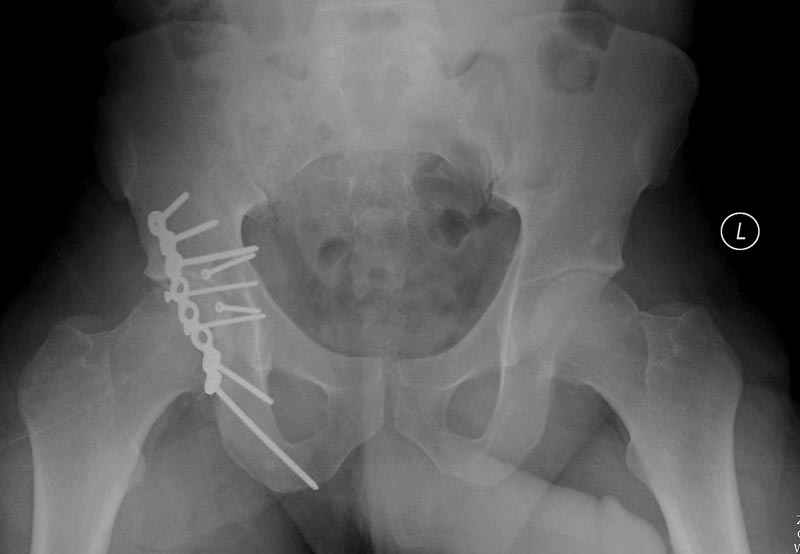

7:30 начало операции, больной на спине, попытка репозиции после анестезии N3, укладка больного на боку, доступ Kocher- Langenbeck, состояние седалищнего нерва около 2.5см кровоподтек, через joistick головка бедра приподнята, освобовождение сустава, фрагмент заднего края более 3х4 см репонирован на свое место. После промывания

сустава, репозиция вывиха (N4), фиксация фрагмента 2.7(4) мм шурупами и допольнительно реконструктивной пластиной на 8 дырок, фиксация 3.5мм шурупами проксимально и дистально.

Интраоперционные N5 косая запирательная и N6 подвздошный снимок

11:50 больной в послеоперационной, рентгенограмма N7, компьютерная томограмма в тот же день N8-10